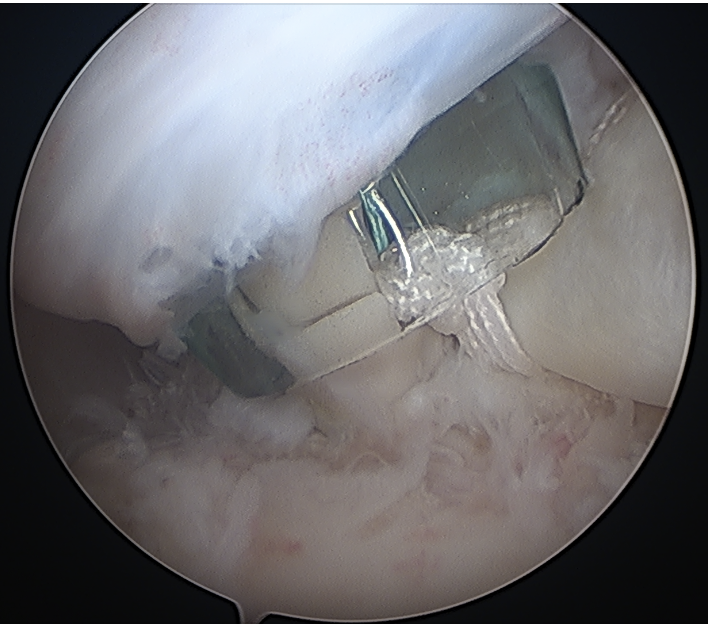

- anchor biceps tendon

Bicortical open subpectoral biceps tenodesis using Arthrex Biceps Button